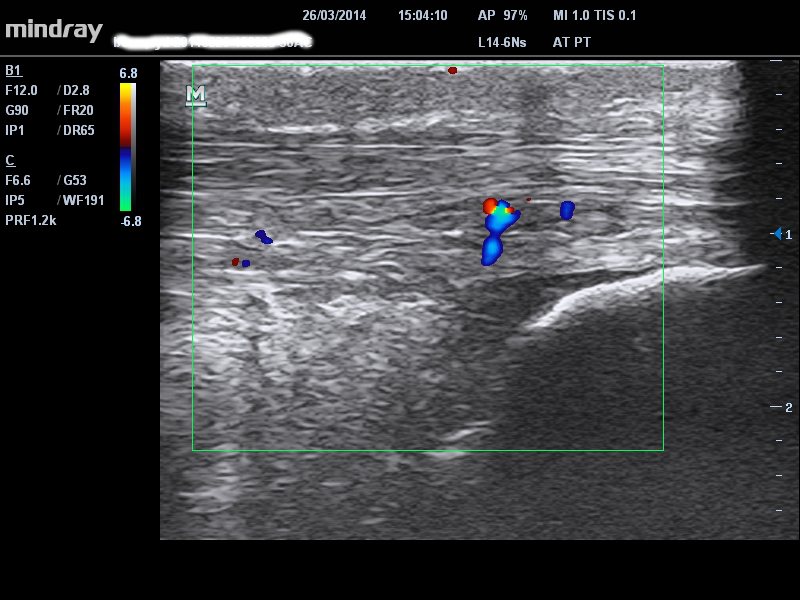

TENDINITIS DE LA INSERCIÓN

La principal diferencia en la tendinopatía de inserción es el sitio del dolor en la inserción distal del tendón de Aquiles ya sea alta (tuberosidad del calcáneo superior) o baja en el calcáneo distal. Hay un patrón similar en el comportamiento del dolor/rigidez matutina y en el ‘calentamiento’ en la tendinopatía de la porción media. El dolor de inserción alto debe diferenciarse de una bursitis retrocalcánea mientras que el dolor de inserción bajo suele ser del tendón. En la ecografía puede haber un espolón de tracción asociado con la inserción baja, pero esto no es necesariamente sintomático – ver espolón de tracción en la figura a continuación.

single-image

3 – patología del tendón de inserción baja con señal Doppler y espolón de tracción